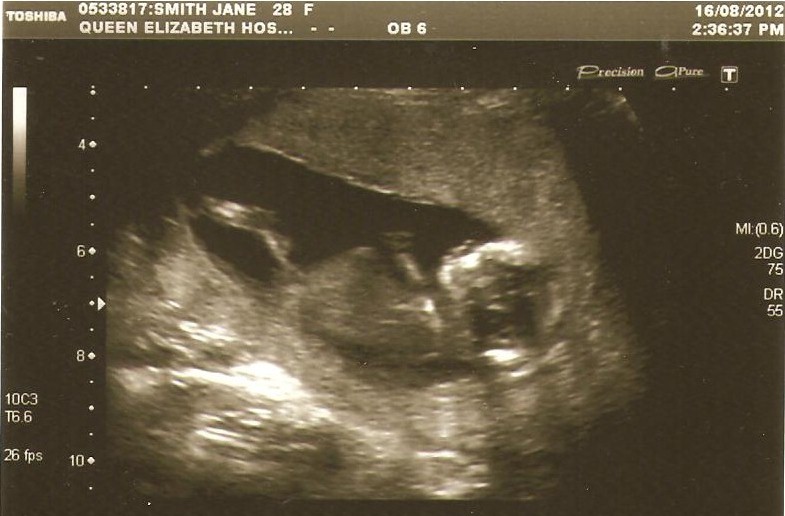

Looks like a baby boy to me! :)

Hard to tell if there is a nub, but the angle would suggest boy?

I see a smaLL sticking out nubby.. isn't that it Ladies?

It appears to be angLed/tiLted upwards so I wiLL also guess :diaper:

Leaning :DS:, the skull looks slightly slanted, even Straight to me! x x